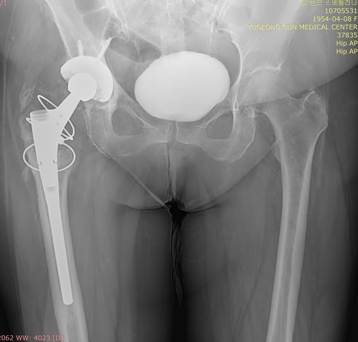

Спасибо всем, принявшим участие в обсуждении случая. Досылаю снимки сделанные две недели назад во время обследования у уролога. Более ранних снимков нет. По анамнезу – оперирована по поводу заболевания (диагноз не знает), травмы не было. На операции раскололи бедро, узнали об этом на следующий день и прооперировали повторно.

Три года чувствовала себя нормально – перестала хромать. Корешковой симптоматики нет.

1. Обсуждаем изображения недостаточного разрешения!!!

2. Думаю, что исходно могла быть диспластичная впадина, поэтому чашка поставлена высоко, немного висит верхний край. Возможно, фрезой просто выбрали многовато вверх. Винты могли быть поставлены не для первичной фиксации чашки, а в связи с традициями конкретной клиники, также по финансовым причинам. Медицинский турист?

3. По нижней части чашки (изображение низкого качества) я вижу линию просветления - резорбция кости? Нестабильность чашки? Чашка сейчас держится в основном на винтах? Боли в паховой области через 4 года после ЭП можно объяснить этим.

4. Имеется бедренная ножка модульной конструкции - это не дефект ножки, а механический узел. Скорее всего это ножка переменной длины - привинчиваешь нижнюю часть подлиннее. Ревизионная? Ножка с переменной антеверсией???Видимо, на повторной операции, увидев расколотую проксимальную часть бедра и невозможность фиксации ножки здесь (что предпочтительнее), пошли на вариант длинная ножка с дистальной фиксацией (бесцементная? Не вижу цементной мантии, возможно она есть, но изображение низкого качества), а проксимальную часть бедра собрали на проволоку или тросы, с замками. Переход на дистальную (скорее всего бесцементную, что считаю ошибкой тактики хирургов) фиксацию ножки предопределил текущую картину. Перенос нагрузок с вертельной области почти в середину диафиза бедра привел к развитию стресс-шилдинга (хорошо видны на прямой проекции гипертрофированные кортикалы на уровне конца ножки), мне видится еще внедрение конца ножки в задний кортикал бедра и щель расшатывания на уровне дистальной трети ножки, могу ошибаться, разрешение низкое. Стресс-шилдинг, нестабильность, давление на кортикал - могут вызывать боли в бедре. Разгрузка проксимальной части закономерно привела к костной резорбции в зоне вертелов. Фиксации данной ножки там не было, нет и уже не будет.

5. Ножку разумнее заменить на цементную, удлинненную, круглую, это распределит нагрузку по кости. Если чашка нестабильна - замена чашки. Возможно на цементную.

Нога правая намного длиннее?

Достоверных клинических и рентгенологических признаков нестабильности компонентов эндопротеза в настоящее время нет. Протез с длинной ножкой и проксимальной модульным компонентом - возможно модульная ревизионная ножка MGS (производство SAMO Италия) бесцементная с проксимальной и дистальный фиксацией. Вероятно была микроподвижность на фоне интраоперационного перелома, на фоне чего произошло утолщение кортикала диафизаtjskl. Часто длинные ножки вызывают болевой синдром в области бедра и при абсолютной стабильности. Иногда прибегают к декомпрессирующей перфорации диафиза дистальнее ножки. Мне кажется, необходимо некоторое время ограничиться динамическим наблюдением и симптоматической терапией так как ревизия будет очень сложной с трудно предсказуемым исходом и потребует специального инструментария и ревизионных компонентов эндопротеза

Необходимо параллельно попытаться исключить инфекционное поражение области эндопротеза, хотя бы косвенно. В случае "спокойных" анализов действительно на сегодняшний день явных достоверных признаков нестабильности компонентов эндопротеза не определяется. Боли в бедре могут быть обусловлены шунтироварием нагрузки в область дистальной фиксации ножки. Динамическое наблюдение.